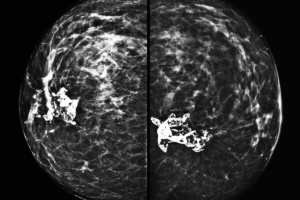

This study was conducted in two phases. A retrospective analysis of earlier acquired three-dimensional transesophageal echocardiography (TEE) datasets was performed in 70 patients, which included 22 with NMV, 26 with RMS, and 22 with severe MAC. Detailed annular, tunnel, and leaflet-tip dimensions were measured by using Philips QLAB software, which includes anteroposterior and intercommissural diameters, valve areas, tunnel length, enclosed valve volume, and orifice orientation angles. Continuous variables were reported as medians with interquartile ranges, and group comparisons were performed by using Student’s t-test or Wilcoxon rank-sum test as appropriate. Statistical significance was defined as P < 0.05 with Bonferroni correction applied for multiple comparisons. Effect sizes and power calculations showed proper statistical power for key anatomic comparisons. Representative patient datasets were used to create 3D silicone valve models of NMV, RMS, and MAC in the second phase. These models were tested in heart flow simulation under controlled conditions by using particle image velocimetry (PIV) to assess transmitral velocity profiles, vortex formation, coefficient of contraction (CoC), pressure gradients, and left ventricular (LV) flow energetics.

The echocardiographic analysis revealed profound geometric differences between MAC, MS, and RMS. The MAC valves showed significantly smaller annular anteroposterior diameter and area compared with RMS (P = 0.003 and P = 0.021, respectively), and intercommissural dimensions were similar. MAC showed a dramatic reduction in anteroposterior diameter and flow area as compared with RMS (P < 0.0001 and P = 0.002) in the valve tunnel. RMS and MAC exhibited reduced dimensions relative to NMV, with no major difference between the two (P > 0.15) at leaflet tips. MAC valves had significantly shorter tunnel length and smaller total mitral valve volume than RMS (both P < 0.0001). These findings indicate that severe functional stenosis in MAC occurs in the annulus and calcified tunnel, and RMS produces a more progressive funnel-shaped narrowing toward leaflet tips.